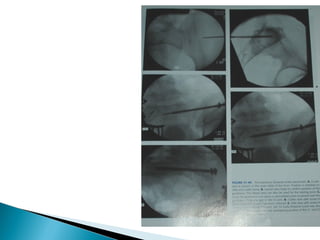

 Retrograde and antigrade pubic ramus fixation:

Retrograde from the pubic tubercle and directed laterally,

Antigrade from the supra acetabular area and directed medially. A

soft tissue sleeve protects the local structures such as spermatic

card from iatrogenic injury.

 Iliac wing fixation:

The percutaneous screw is inserted from AIIS, above the greater

sciatic notch, and terminating in posterior iliac crest.

 Sacral fractures:

length of screw is inserted perpendicular to fracture

line. A lag screw can be used for compression and a

second full threaded screw for support to post pelvic

fixation.

 Trans iliac rod fixation of sacral Fractures:

Two rods are passed from outer aspect of one

ilium through the opposite ilium and nuts tightened

over threaded ends to apply compression.